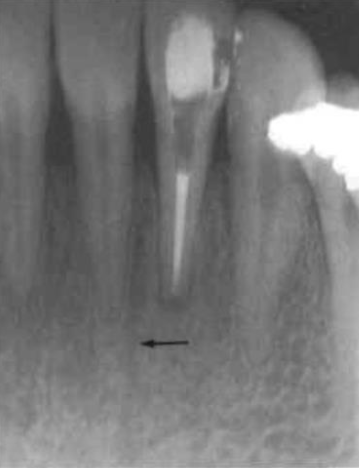

mandibular canal

aka: inferior dental canal

runs from the mandibular foramen in the ramus to the mental foramen

seen as a radiolucent band and may lie in close association with the apices of molar and 2nd premolar teeth

extrusion of medicaments and root canal filling materials may damage the inferior dental bundle

mental foramen

located below and distal to the apex of the 1st premolar

may be mistaken for a pathological lesion when it appears close to the apex of one of the premolars, which is due to the angle at which the radiograph is taken